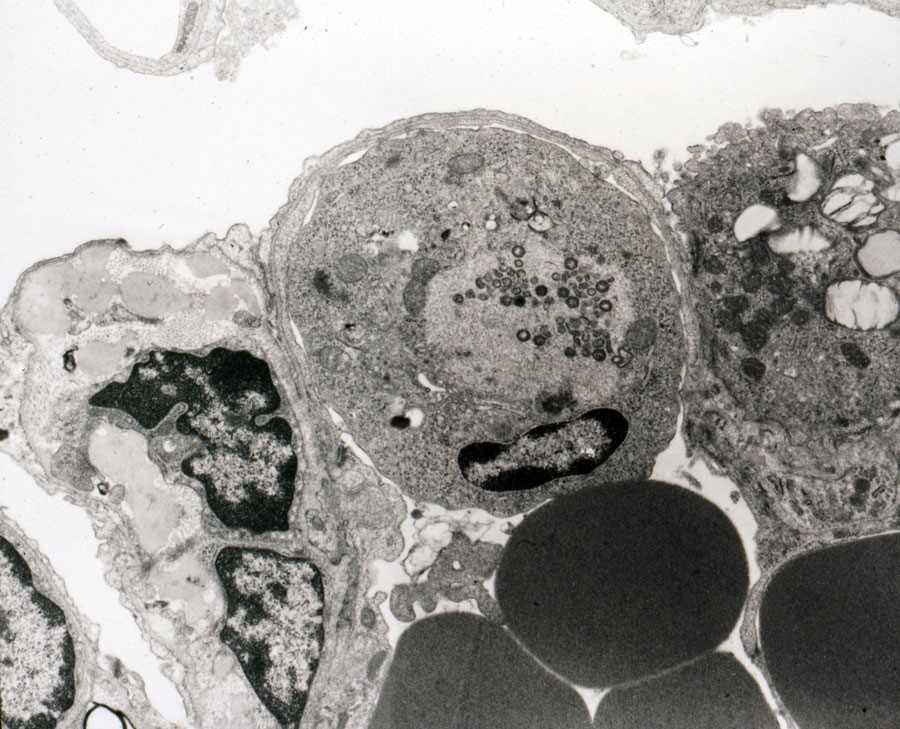

Макрофаг, пораженный вирусом африканской чумы свиней